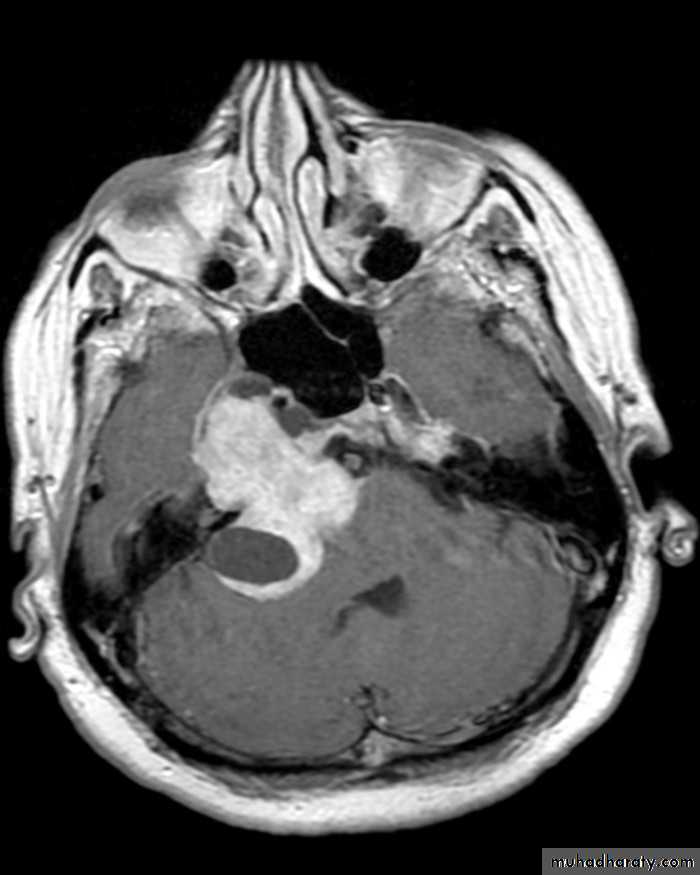

MEDULLOBLASTOMA AXIAL MRI